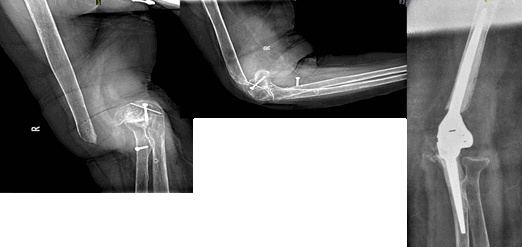

В 168 случаях в нашу клинику обращались пациенты, перенесшие оперативные вмешательства на локтевом суставе. По нашим наблюдениям, выбор металлоконструкций не являлся определяющим с точки зрения хирургического разрешения проблемы перелома плечевой и (или) локтевой кости. К данной группе мы отнесли пациентов с металлоконструкциями (спицы, винты, накостные пластины и т.д.) и с удаленной металлоконструкцией. Характерными особенностями данной группы стали:

- огромное количество рубцовой ткани в области локтевого сустава,

- нейропатия одного или нескольких периферических нервов,

- гипертрофированные или втянутые кожные рубцы,

- остеолиз с формированием ложного сустава или обширные костные разрастания со стойкой контрактурой.

Интраоперационно, помимо необходимости удаления металлоконструкции, возникала необходимость выполнять кожную пластику, невролиз, костную пластику. В 3 случаях во время обработки костно-мозгового канала мы столкнулись со склерозной перестройкой костной ткани, потребовавшей дополнительно к эндопротезированию выполнить канатный остеосинтез. Объем движений во время операции достигал 0-0-150. В послеоперационном периоде пациентам требовалась помощь неврологов, специалистов отделения восстановительного лечения и терпение для достижения удовлетворительного результата. Однако через год на контрольном осмотре отмечалось ограничение движений в локтевом суставе (0-30-110) и необходимость нейрохирургической коррекции (рис. 4).

Рис. 4. Тотальное эндопротезирование при «болтающемся» локтевом суставе